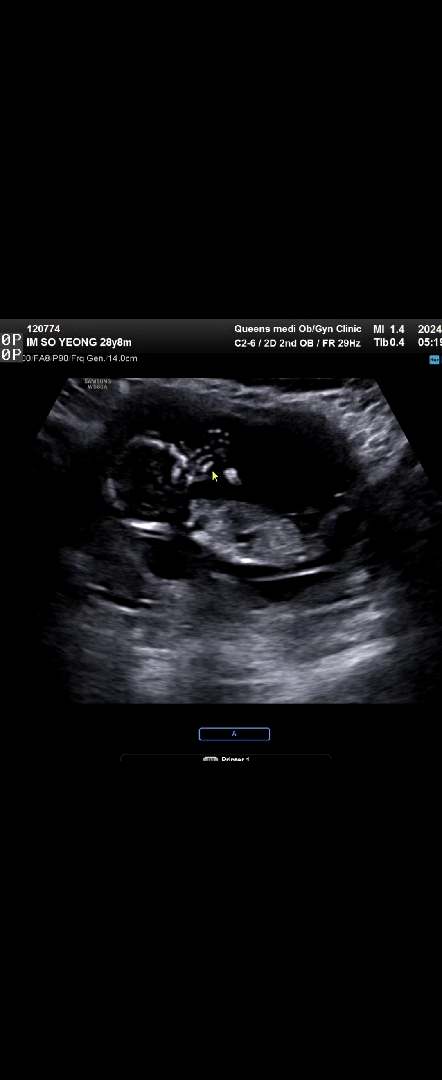

12주차입니다~ 각도법 좀 봐주세요!

딸일까요 ? 아들일까요 ? 손가락을 쫙피고 있어서 손가락은 너무 잘보이네요 ㅎ